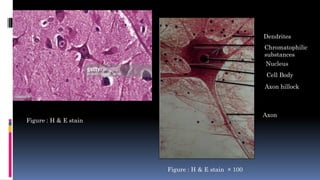

Dendrites

Chromatophilic

substances

Nucleus

Cell Body

Axon hillock

Axon

Figure : H & E stain

Figure : H & E stain × 100